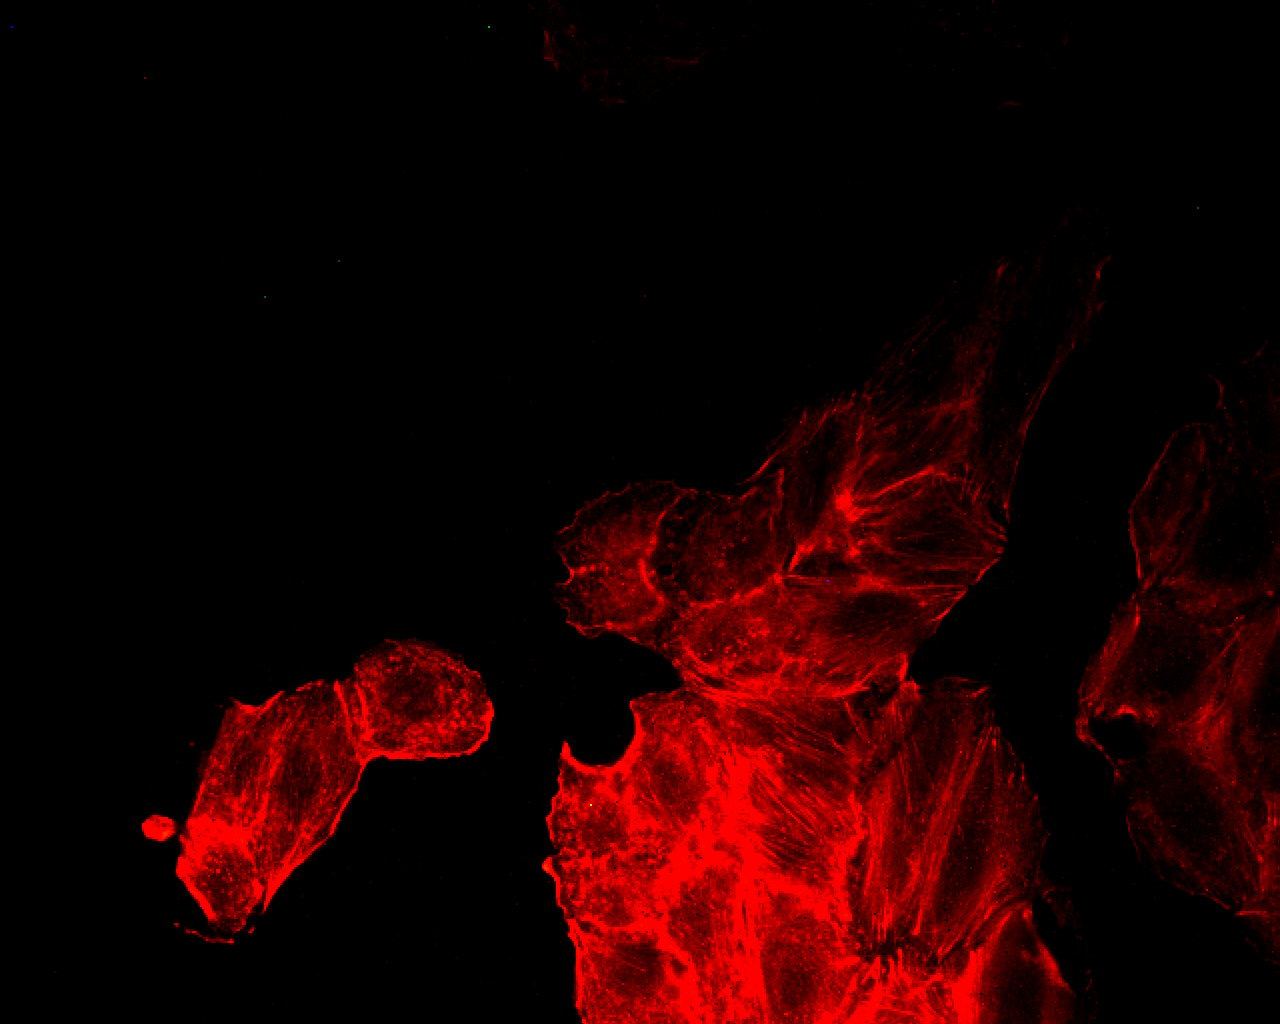

Immagine di Hypothalamus via Wikimedia pubblicata su licenza Creative Commons Attribution-Share Alike 3.0 Unported